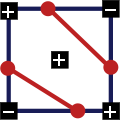

Как всегда начнем со схемы, вычисления выполняются для каждого среза.

1. Три квадрата одного знака и один противоположного, движение контура происходит по диагонали:

2. Два квадрата одного знака и два противоположного, причем квадраты с одинаковым знаком находятся по одну сторону, движение контура идет вертикально или горизонтально:

3. Два квадрата одного знака и два противоположного, квадраты с одинаковыми знаками размещены по разные стороны:

Это является исключительным случаем, чтобы принять решение берется среднее значение интенсивности во всех четырех квадратах, и если оно больше или равно порогу, то центр положителен, в остальных случаях — отрицателен. Также важно какой узел является текущим в данный момент:

Конкретно первый и второй случаи: